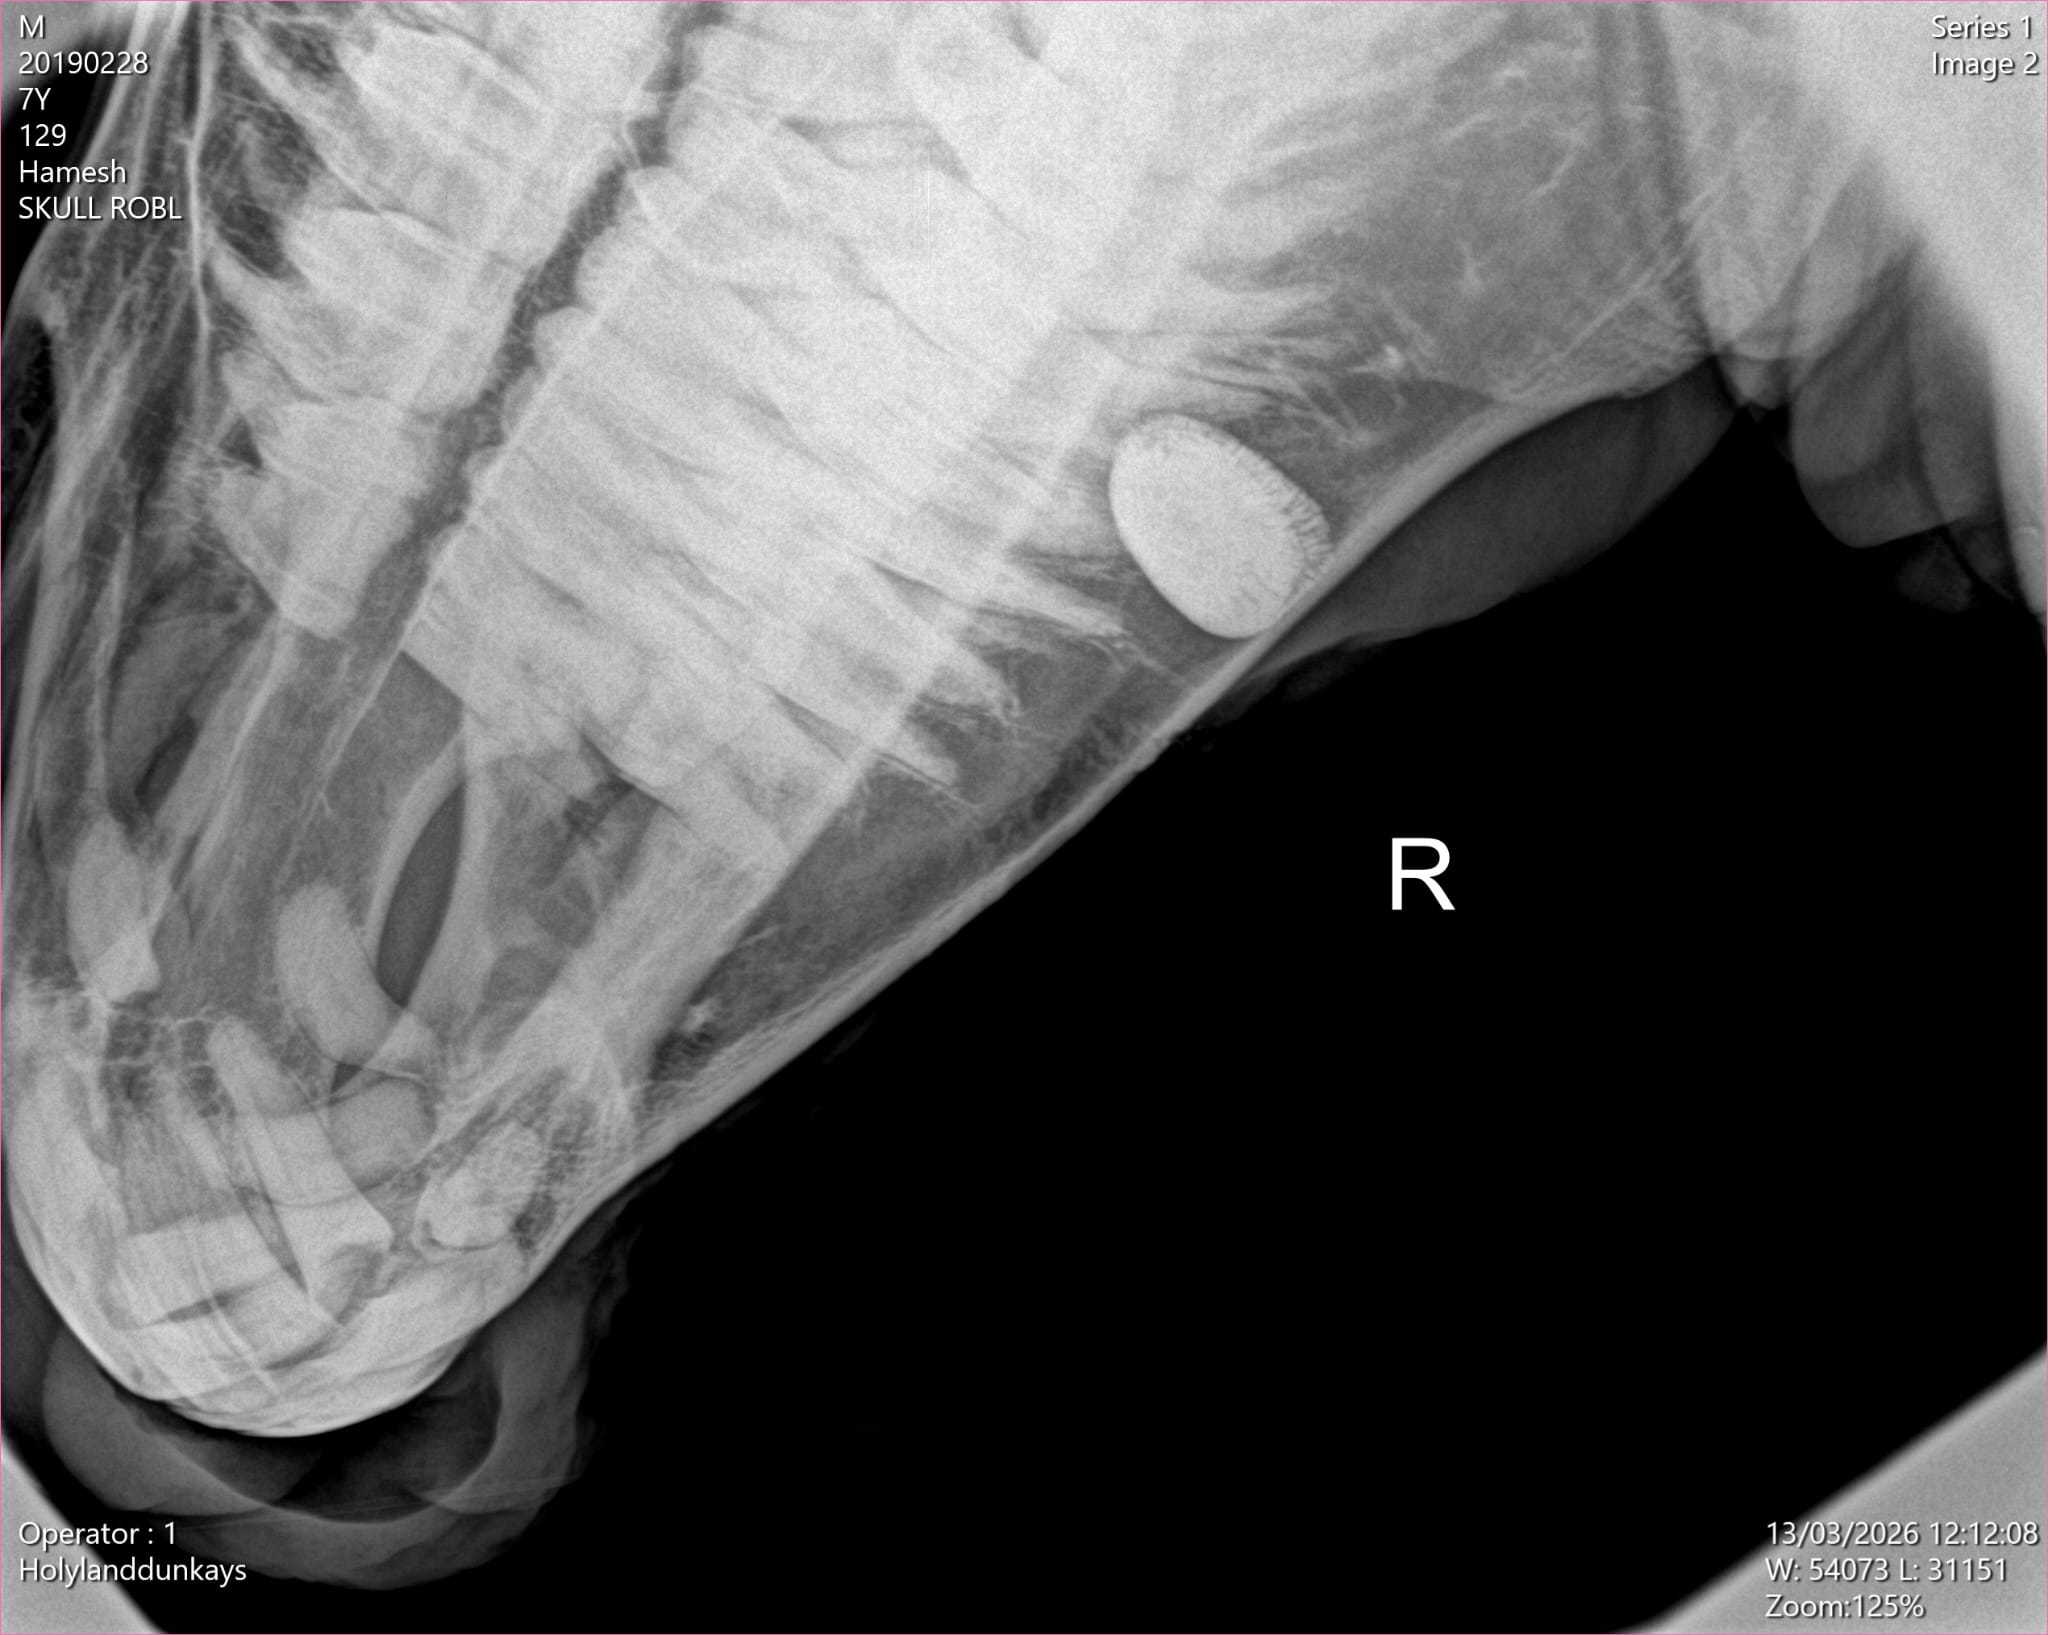

An x-ray showed a large build up of tartar in Hamish’s mouth.

To understand the issue fully, Hamish had an X-ray, which clearly showed the build-up. Our vet, Rafik, then carried out a simple procedure to remove the tartar. Thanks to your support, Hamish is now much more comfortable and happily back with his herd.